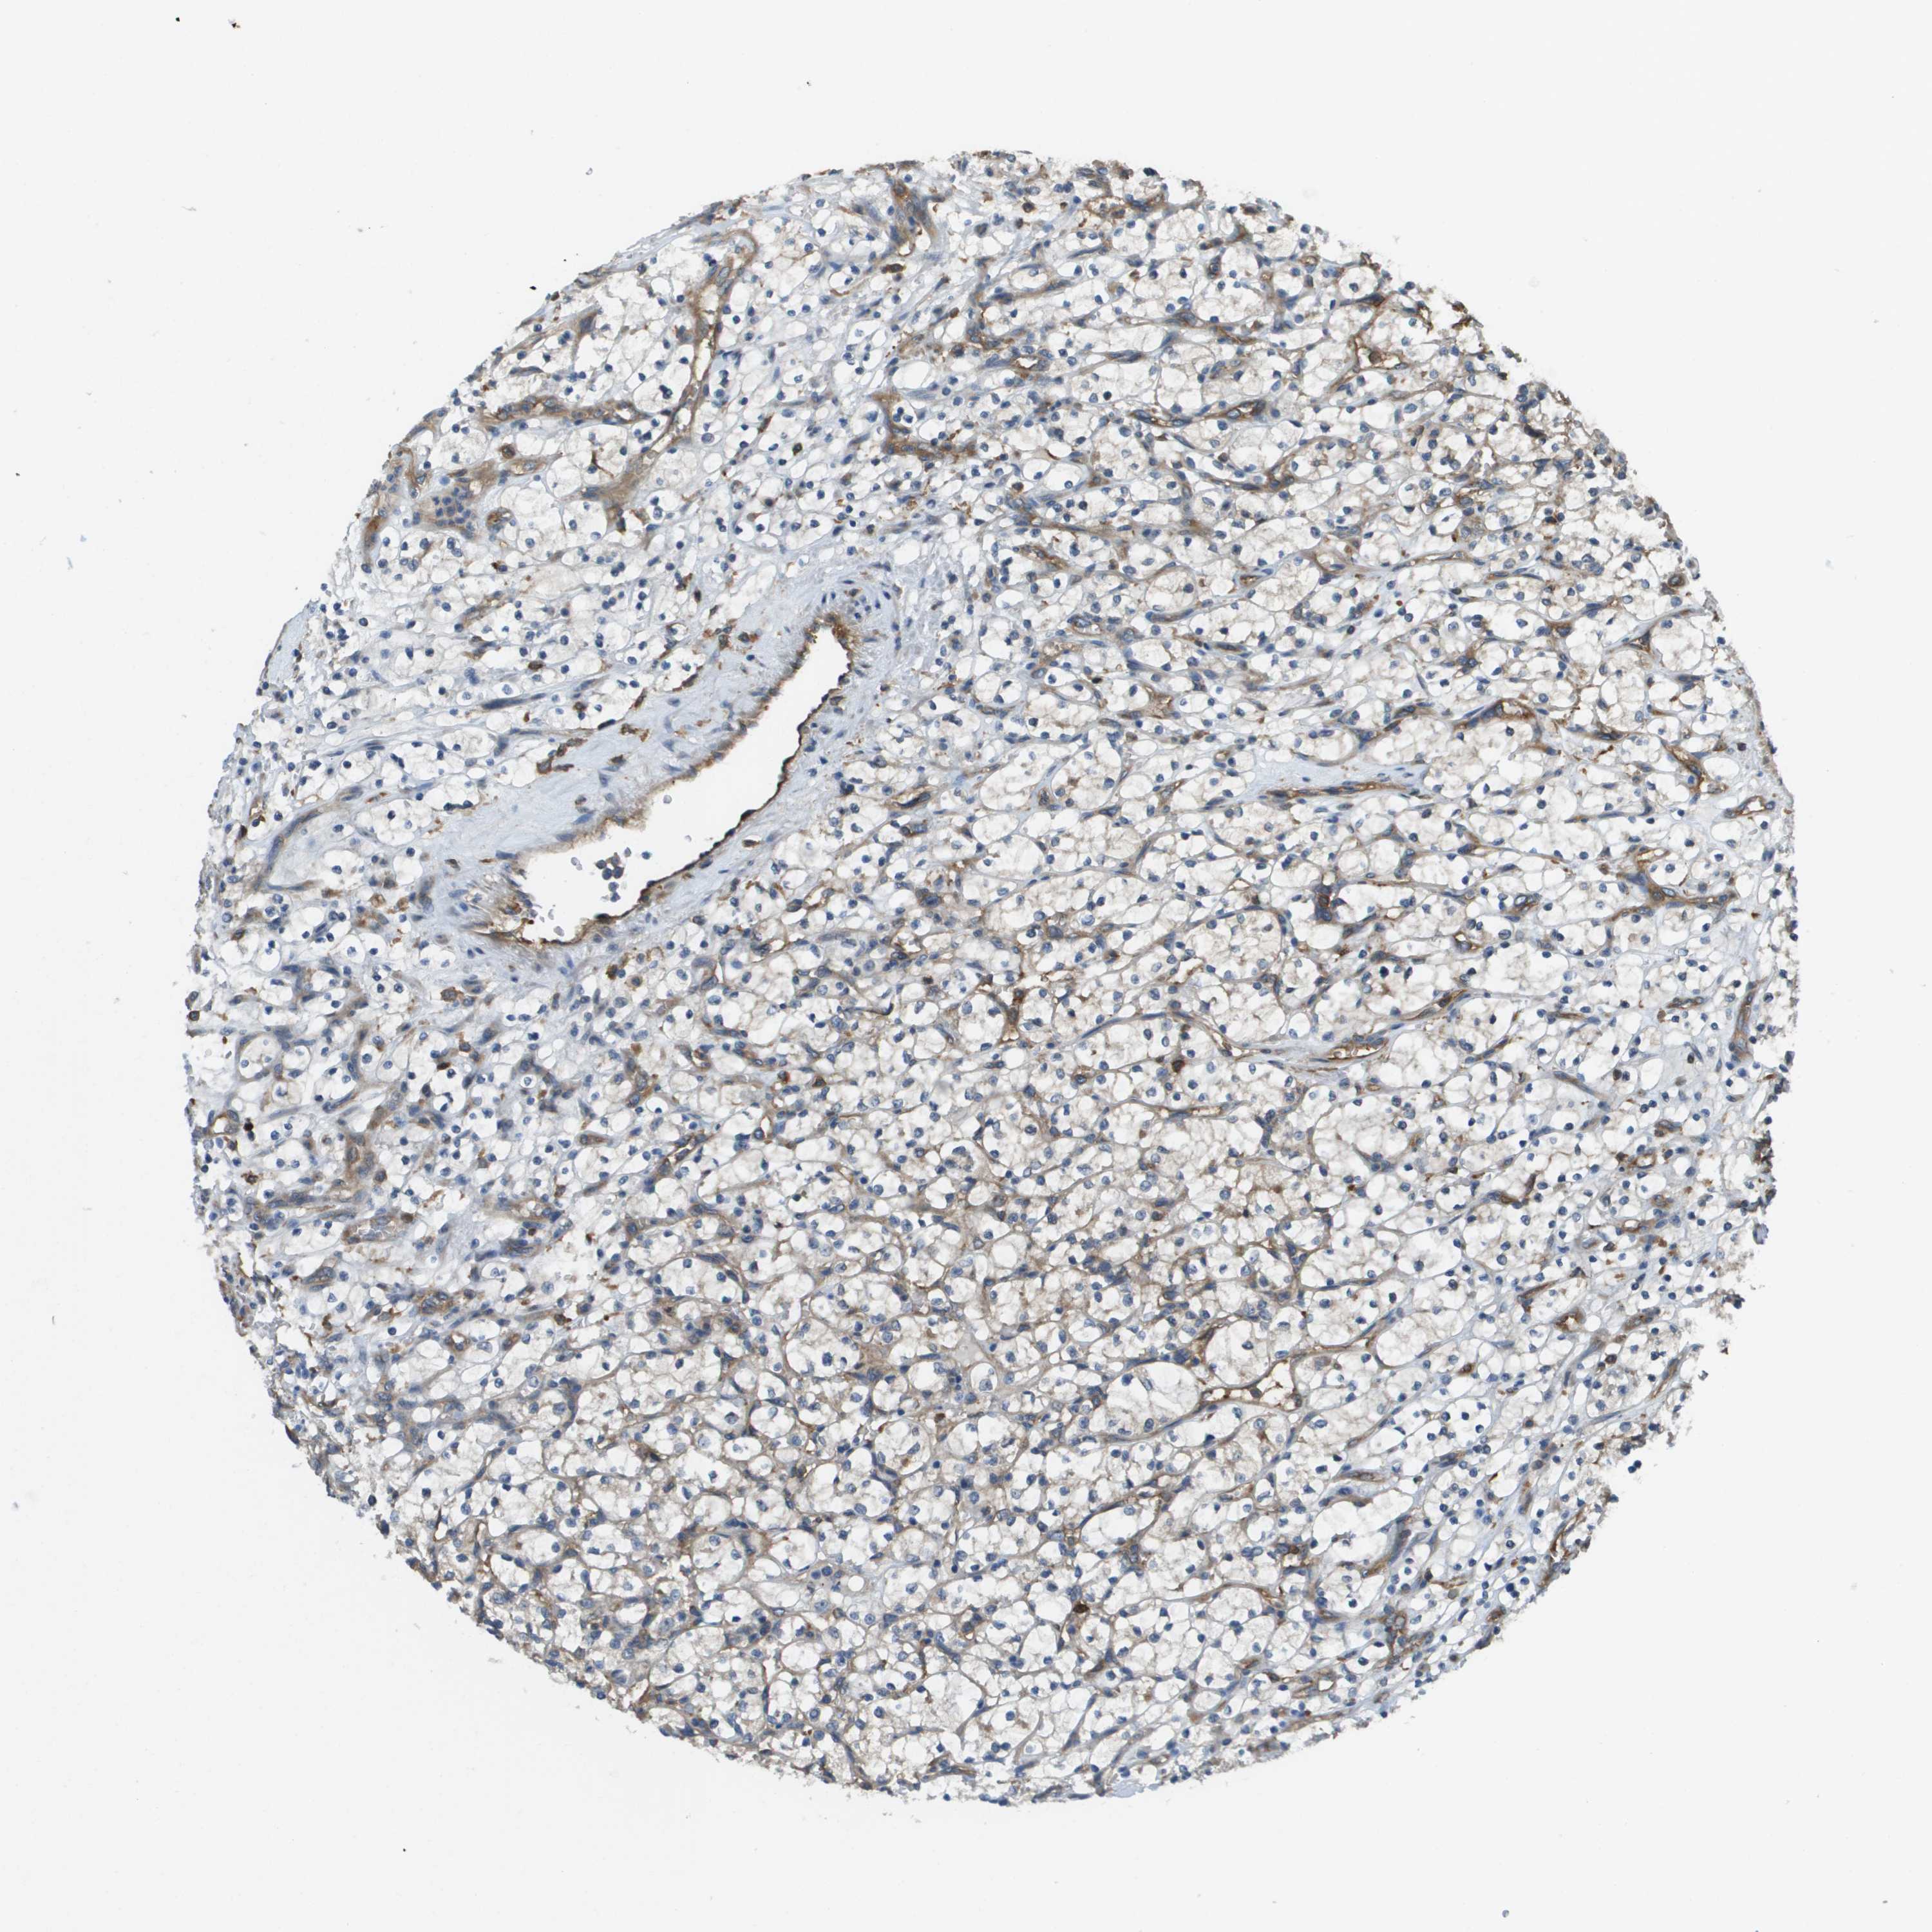

KIDNEY RENAL PAPILLARY CELL CARCINOMA (TCGA) - Interactive survival scatter ploti

The Survival Scatter plot shows the clinical status (i.e. dead or alive) for all individuals in the patient cohort, based on the same data that underlies the corresponding Kaplan-Meier plots. Patients that are alive at last time for follow-up are shown in blue and patients who have died during the study are shown in red.

The x-axis shows the expression levels (FPKM) of the investigated gene in the tumor tissue at the time of diagnosis. The y-axis shows the follow-up time after diagnosis (years). Both axes are complimented with kernel density curves demonstrating the data density over the axes. The top density plot shows the expression levels (FPKM) distribution among dead (red) and alive patients (blue). The right density plot shows the data density of the survived years of dead patients with high and low expression levels respectively, stratified using the cutoff indicated by the vertical dashed line through the Survival Scatter plot. This cutoff is automatically defined based on the FPKM cutoff that minimizes the p-score. The cutoff can be changed by dragging the vertical line or by entering a cutoff value in the square labeled "Current cut-off".

Under the Survival Scatter plot the p-score landscape (black curve; left axis) is shown together with dead median separation (red curve; right axis). Dead median separation is the difference in median mRNA expression between patients who have died with high and low expression, respectively. It is calculated as follows: median FPKM expression of dead patients with high expression - median FPKM expression of dead patients with low expression. This is intended to aid the user in visually exploring custom cutoffs and the associated p-scores and dead median separation.

Individual patient data is displayed and can be filtered by clicking on one or more of the category buttons on the top of the page. Categories describing expression level and patient information include: high, low, alive, dead, female, male and tumor stages. The scale of the x-axis can be toggled between linear and log-scale by clicking on the "x log" button. Mouse-over function shows TCGA ID, patient information and mRNA expression (FPKM) for each patient.

& Survival analysisi

Kaplan-Meier plots summarize results from analysis of correlation between mRNA expression level and patient survival. Patients were divided based on level of expression into one of the two groups "low" (under cut off) or "high" (over cut off). X-axis shows time for survival (years) and y-axis shows the probability of survival, where 1.0 corresponds to 100 percent.

CORO1B is not prognostic in Kidney Renal Papillary Cell Carcinoma (TCGA)

Best expression cut offi

Based on the FPKM value of each gene, patients were classified into two groups and association between prognosis (survival) and gene expression (FPKM) was examined. The best expression cut-off refers the FPKM value that yields maximal difference with regard to survival between the two groups at the lowest log-rank P-value. Best expression cut-off was selected based on survival analysis .

When clicking on this number, the vertical dashed line indicating cut-off, the interactive survival plot, and the Kaplan-Meier curve will be adjusted to show results based on the best expression cut-off.

: 75.49